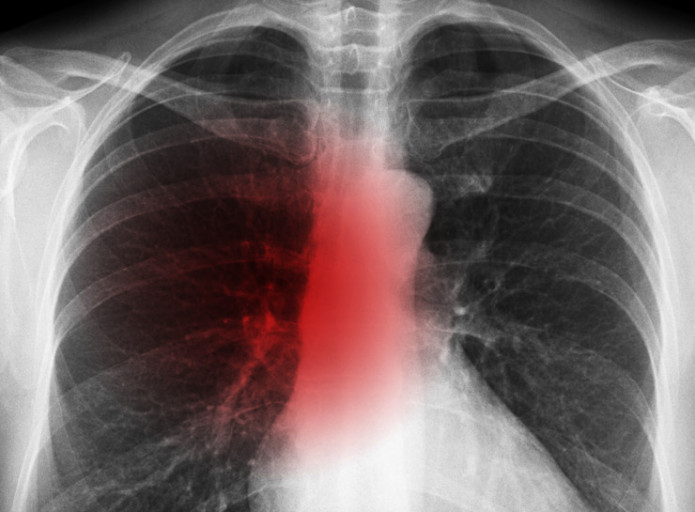

- 호흡 곤란 및 가슴 통증

- 설명: 폐렴의 가장 심각하고 중요한 증상입니다. 폐에 염증이 생겨 폐 기능이 떨어지면서 숨쉬기 힘들어지며, 얕고 빠른 호흡을 하게 됩니다. 심한 경우 가슴에 통증을 느끼거나, 옆구리가 결리는 듯한 느낌을 받을 수 있습니다.